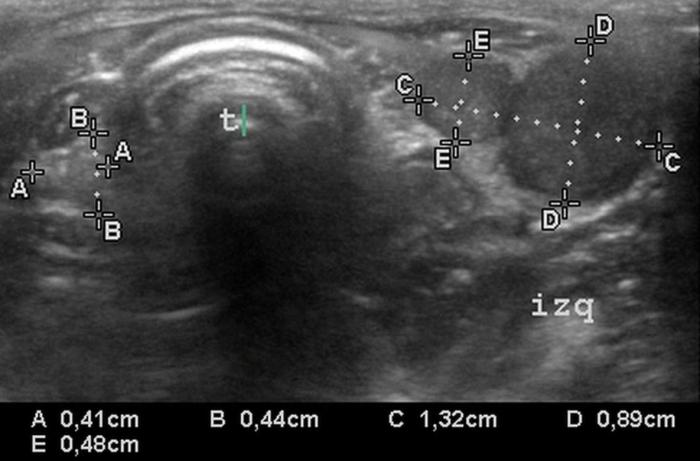

Relación entre el área transversal de la glándula tiroides (TG) y de la arteria carótida común (CCA)

El índice TG/CCA es una herramienta ecográfica cuantitativa propuesta para la evaluación del tamaño tiroideo en perros, particularmente útil cuando se sospecha de hipoplasia glandular o hipotiroidismo12. Este índice se calcula mediante la medición del área transversal del lóbulo tiroideo (TG) y la comparación con el área de la arteria carótida común (CCA) adyacente, ambas obtenidas en un corte transversal a nivel medio cervical8.

Para su obtención, el animal se posiciona en decúbito dorsal con el cuello extendido. Se utiliza un transductor lineal de alta frecuencia (mínimo 10 MHz), y se realiza una imagen transversal donde se identifican claramente el lóbulo tiroideo y la arteria carótida. Se mide el área de cada estructura mediante trazo elíptico o libre, dependiendo de la morfología. La relación se expresa como TG/CCA, un valor adimensional que permite estandarizar la evaluación tiroidea en animales de distinto tamaño corporal7.

En perros clínicamente sanos, se ha reportado un valor promedio de TG/CCA de 1.53 en promedio12. Valores consistentemente bajos pueden sugerir atrofia glandular o hipoplasia, siendo útiles para apoyar el diagnóstico de hipotiroidismo en pacientes con hallazgos clínicos y laboratoriales compatibles. Según Sasaki et al. (2020), si se utiliza el valor de corte <1.12, el índice TG/CCA indica hipotiroidismo con una sensibilidad del 100 %, una especificidad del 83 % y una precisión del 90 %.

Este índice se ha mostrado reproducible, poco afectado por el tamaño corporal o la edad, y puede ser una herramienta de utilidad en estudios longitudinales o de seguimiento terapéutico. Si bien su uso no reemplaza las pruebas hormonales específicas, constituye un complemento objetivo y no invasivo dentro del algoritmo diagnóstico ecográfico de la glándula tiroides en perros4.

Relación entre el diámetro tiroideo (TD) y el diámetro de la arteria carótida común (CCA)

El uso de estructuras vasculares adyacentes como referencias anatómicas ha sido una estrategia útil en ecografía veterinaria para estandarizar las mediciones de órganos pequeños como la glándula tiroides. En este contexto, Bandula Kumara et al. (2019) propusieron la medición de la relación entre el diámetro tiroideo (TD) y el diámetro de la arteria carótida común (CCA) como una forma práctica de evaluar el tamaño de la glándula en perros clínicamente normales (Figura 5A-B).

Los autores realizaron un estudio en el que midieron el diámetro anteroposterior de los lóbulos tiroideos y el diámetro externo de la CCA en cortes transversales obtenidos a nivel del cuello medio. Encontraron que esta relación se mantiene relativamente constante entre razas y tamaños corporales, sugiriendo que puede ser utilizada como parámetro de referencia ecográfica. Específicamente, en perros adultos sanos, la relación TD/CCA fue de 1.74 ± 0.40 (rango 1.11–2.43)6. Si los valores se encuentran por debajo del rango normal pueden ser considerados potencialmente indicativos de hipoplasia tiroidea o atrofia glandular.

Una ventaja de esta relación es que la arteria carótida común es fácilmente identificable ecográficamente, presenta un diámetro estable y poco variable en condiciones fisiológicas, y se ubica en estrecha proximidad con la glándula tiroides. Esto la convierte en una excelente estructura de referencia para normalizar mediciones entre individuos de diferente tamaño corporal, permitiendo evaluaciones objetivas en poblaciones mixtas de perros de compañía.

Además, este índice podría tener aplicación clínica en el seguimiento de animales con enfermedad tiroidea subclínica o en tratamiento, ya que permite detectar cambios discretos en el volumen glandular con buena reproducibilidad interobservador. Aunque su utilidad clínica requiere aún validación en animales con patología confirmada, representa una herramienta complementaria valiosa dentro del enfoque ecográfico sistemático de la glándula tiroides en pequeños animales.